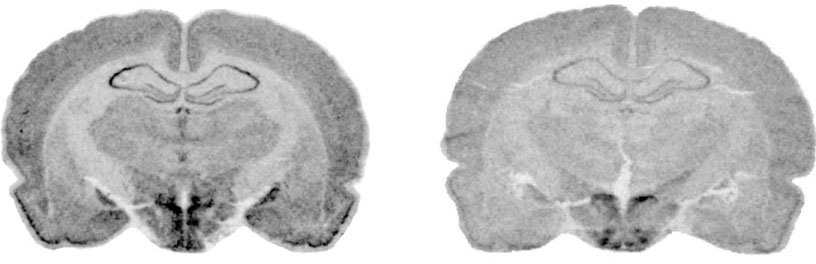

Our unit currently comprises the housing room and some laboratories of the Pharmacology department where we are able to conduct projects involving a limited number of animals (rats and mice). One of the laboratories is used for in vivo models, with two stereotaxic units for brain surgery procedures; the other laboratory has microtome and cryostat equipment for cutting histological sections which are used for all the colorimetric, immunofluorescence and immunohistochemistry assays, cell degeneration assays, and in situ hybridisation for detecting levels of expression of specific mRNAs. After histological sections have been viewed under the microscope, the images can be analysed. We also have a laboratory equipped for performing implantation surgery of brain dialysis probes (mice and rats) and for obtaining samples from freely-moving animals; a further laboratory is used for assaying neurotransmitters and/or substances derived from brain dialysate.

• cell degeneration (stainings such as Fluoro-Jade, Propidium Iodide, Silver Staining, Hoechst 33342);

• MCID Image analysis

AF-S Histological staining on tissue sections or on primary cultures (fluoro-jade or propidium iodide or silver staining or Hoechst): 10 slides (favourable rates can be arranged according to the number of samples to be examined and slides required) 220.00

AF-IA Images acquisition by fluorescence microscope Leica DMRA2 and analysis of images by MCID (specialized assistance) 55.00/hour

250.00/day